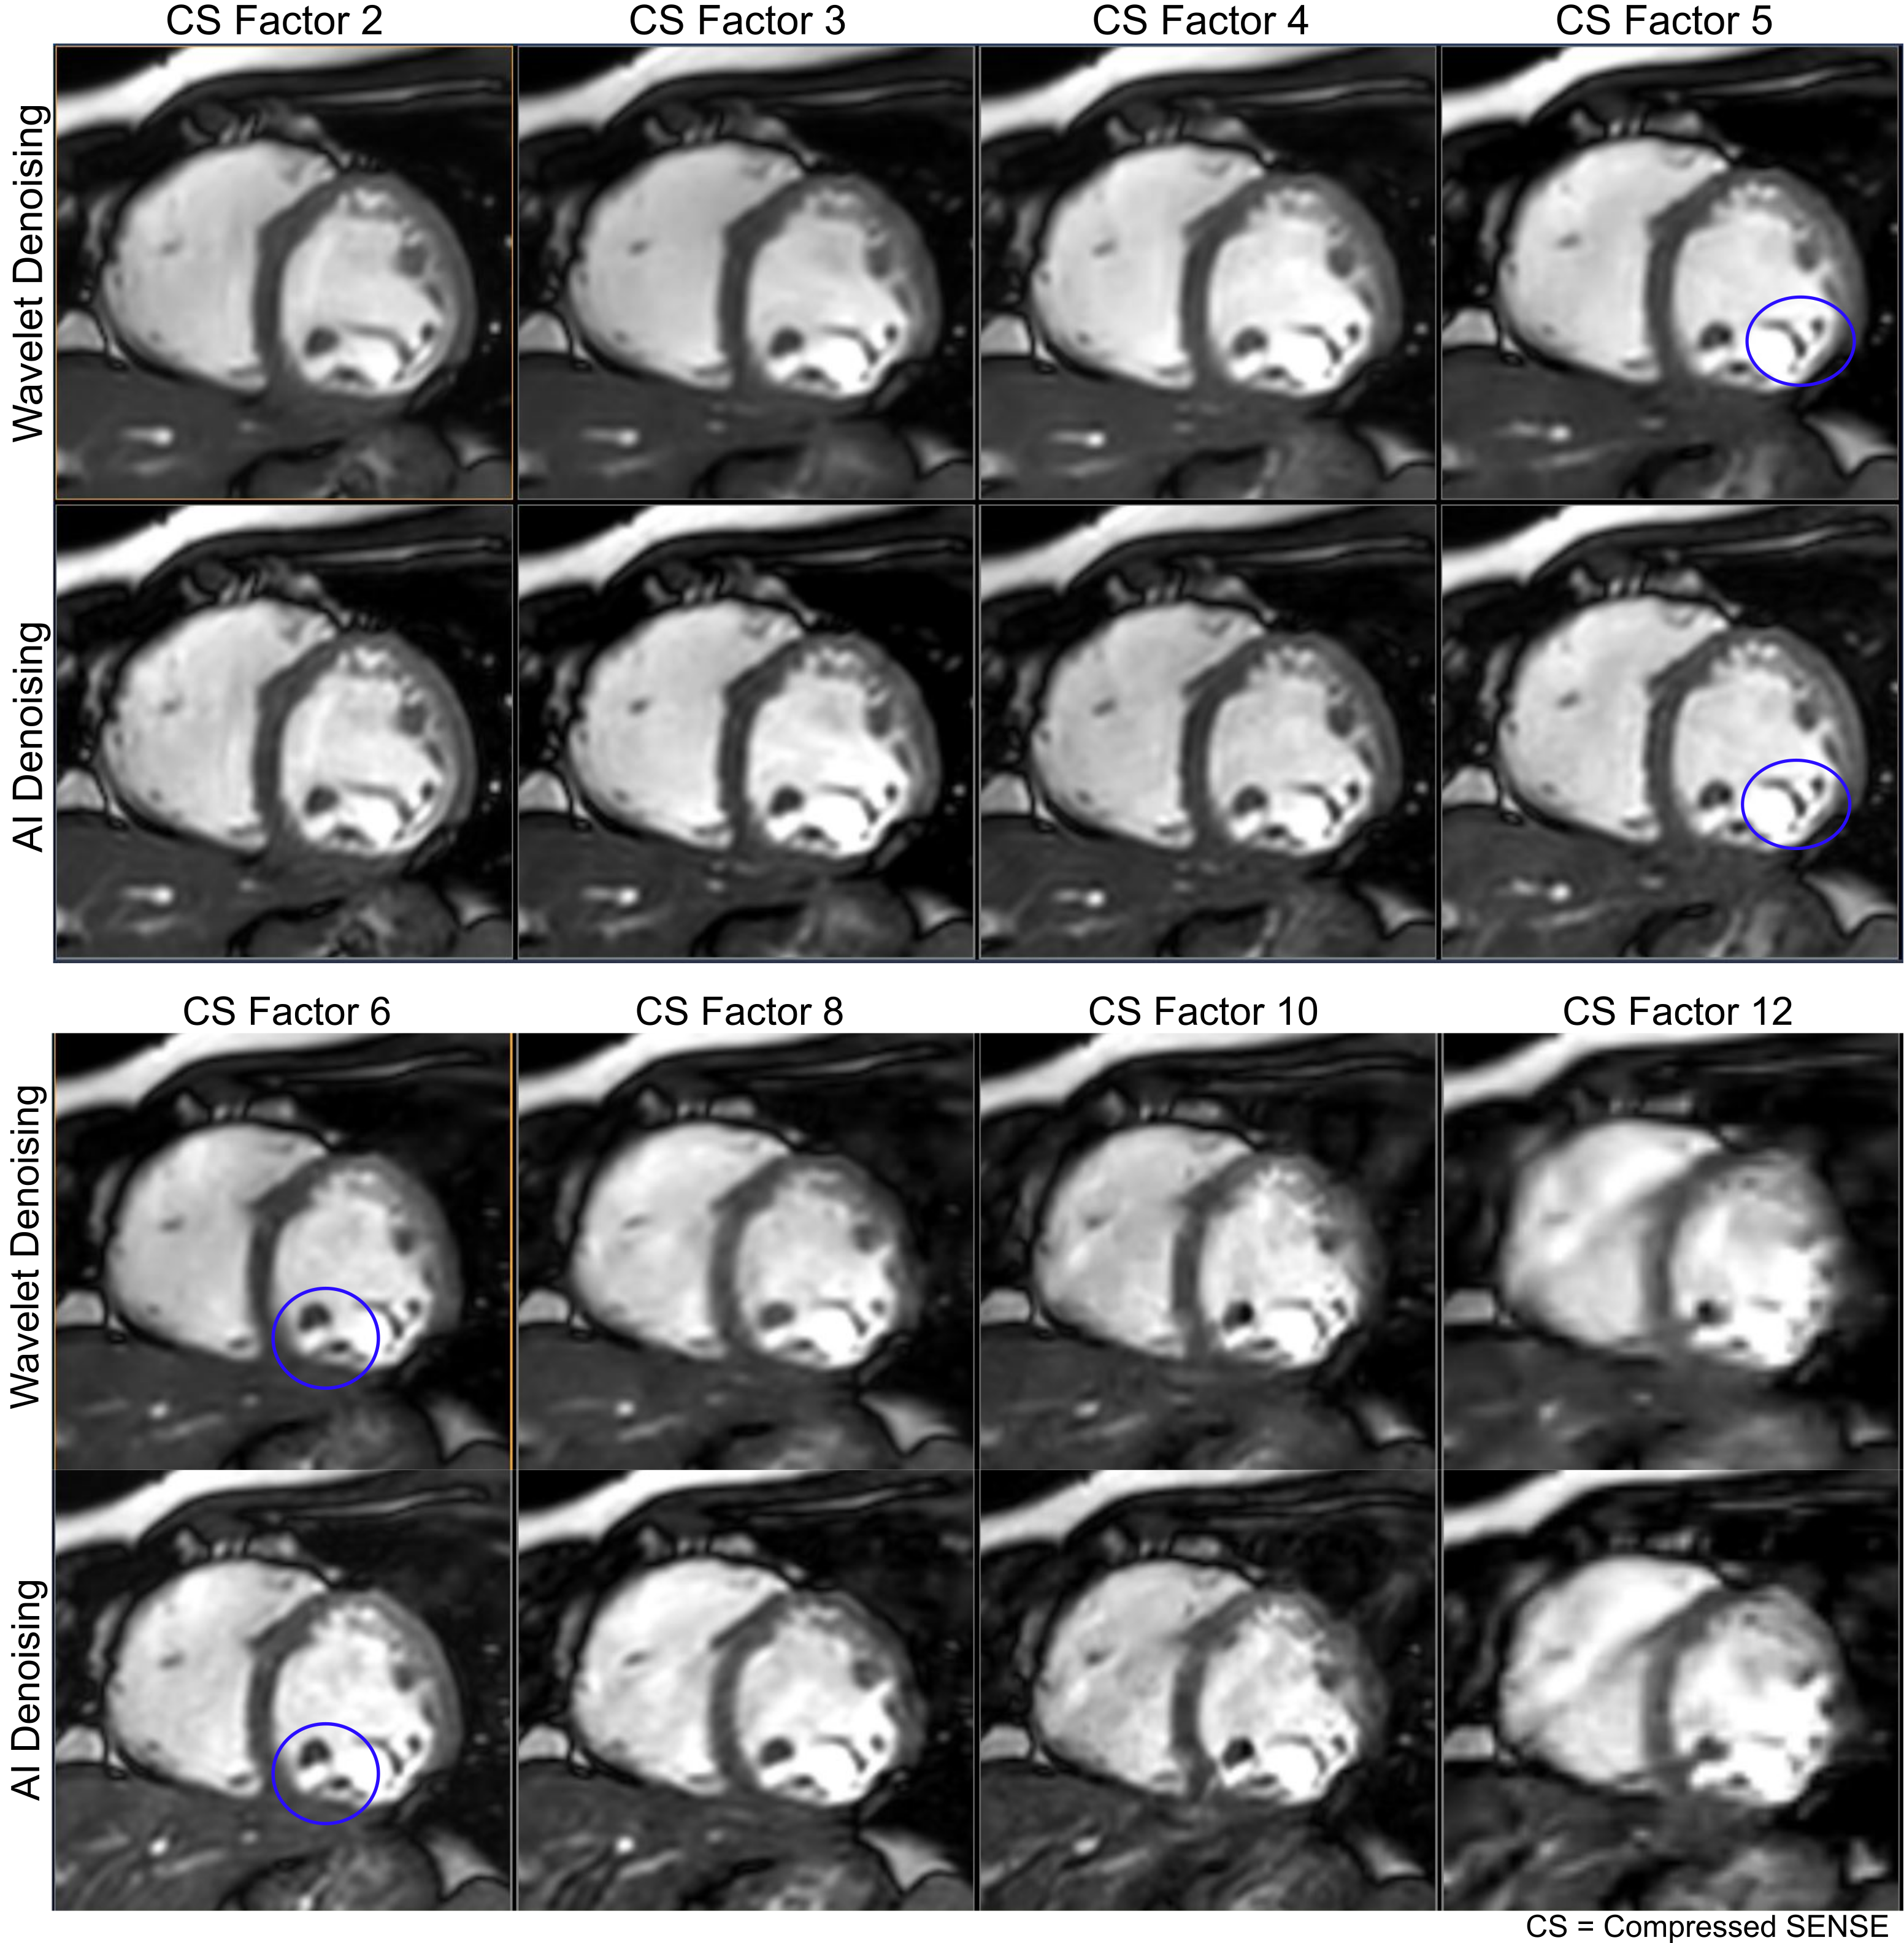

Figure 2. Averaged gradings from four blinded readers for five different image quality metrics in categories overall image quality, blurring, perceived SNR, susceptibility artifacts, and aliasing. Higher acceleration factors were included as this study progressed, resulting in different n for different acceleration factors. Sample sizes indicate data included for both standard and AI reconstructions. Image quality metrics are improved for AI reconstruction, especially for higher compressed sense factors and the blurring metric. (SNR signal-to-noise ratio, AI artificial intelligence)